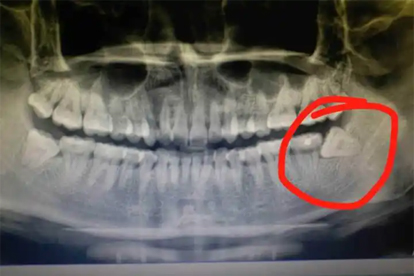

横向或斜向生长的阻生智齿持续压迫牙龈,可能引起慢性炎症反复发作。通过口腔全景片检查智齿位置,若存在邻牙损伤风险,需手术拔除。术前可使用布洛芬缓释胶囊缓解疼痛。

极少数情况下,智齿区肿痛可能与含牙囊肿或成釉细胞瘤有关。CT检查可见骨质吸收或占位性病变,需行病理活检确诊。治疗需手术切除病灶并送检,术后配合头孢克肟分散片预防感染。